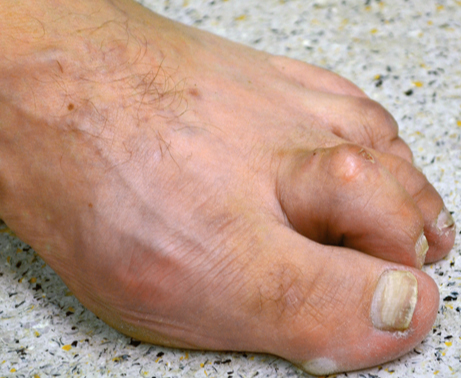

The Hallux valgus (balltoe)

Hallux valgus - in linguistic usage frequently called ball toe - concerns a deviation of the large toe outward, small toes upward. This deformity is more common by women. The exact Cause is not clarified, of course wrong Footwear and hereditary factors play a large role. The different versions are marked by increased deformity and accompanied by pain.

Claw Toe

The claw toe or hammer toe describes a deformity or curvature of the small toe. By increasing the shortening first digital flexor tendon in the middle joint, then the extensor tendon in the base joint, there is a curvature of the toe. In this way, pain and cornifications occur under the ball of the foot, and painful pressure points on the interphalangeal joints (corns). This deformity can usually only be corrected surgically. By an extension of the extensor tendon and solution of the joint capsule, together with a stiffening means in the toe joint, the toe is straightened permanently. The pressure points and relieves pain.